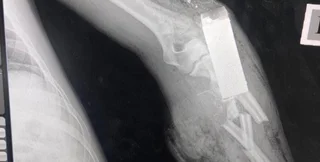

Из тела украинского защитника военные врачи достали боевой элемент гранаты | Фото: Медичне командування ЗСУ

По словам медиков, элемент гранаты попал военнослужащему в руку.

"То, что вы видите на фото — боевой элемент гранаты ВОГ-17, который попал прямо в руку украинского защитника. К счастью, наши военные врачи достали его из руки раненого, спасая ему не только жизнь, но и конечность", — говорится в сообщении.